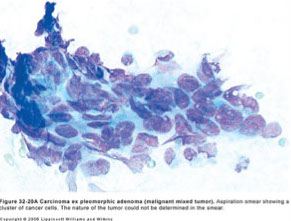

Malignant Mixed Tumor

Malignant Mixed Tumor

Can occur in 3 situations:

- Carcinoma ex pleomorphic adenoma

- metastasizing mixed tumor

- carcinosarcoma

Carcinoma ex PA is the MCC

- risk up to 1/10 for PAs present > 15 years

- may be able to tell clinically if mass is rapidly enlarging and painful

Metastasizing mixed tumor is a b9 PA that has met'd

- usually assoc c some type of surgery to a PA

- even though looks b9, this thing is usually lethal

Carcinosarcoma is rare

- should be able to recognize epithelial and mesenchymal cells

Carcinoma ex PA